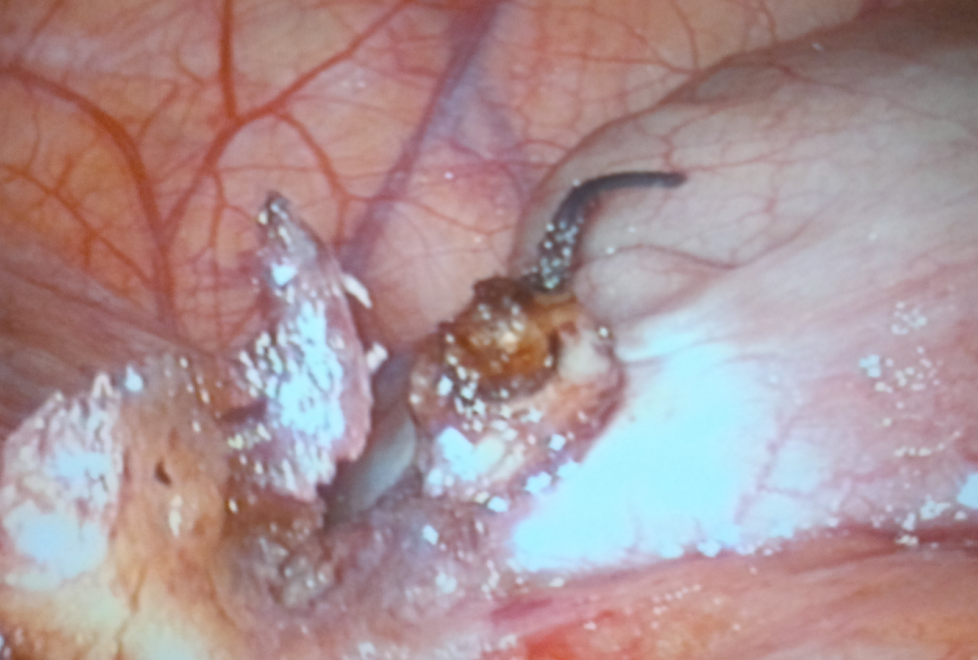

Treo ruột thừa lên thành bụng hố chậu phải bằng một sợi chỉ đâm xuyên qua thành bụng.

Tiến hành cầm máu mạc treo và cắt mạc treo.

Buộc gố ruột thừa bằng Vicryl 2.0 và cắt gốc.